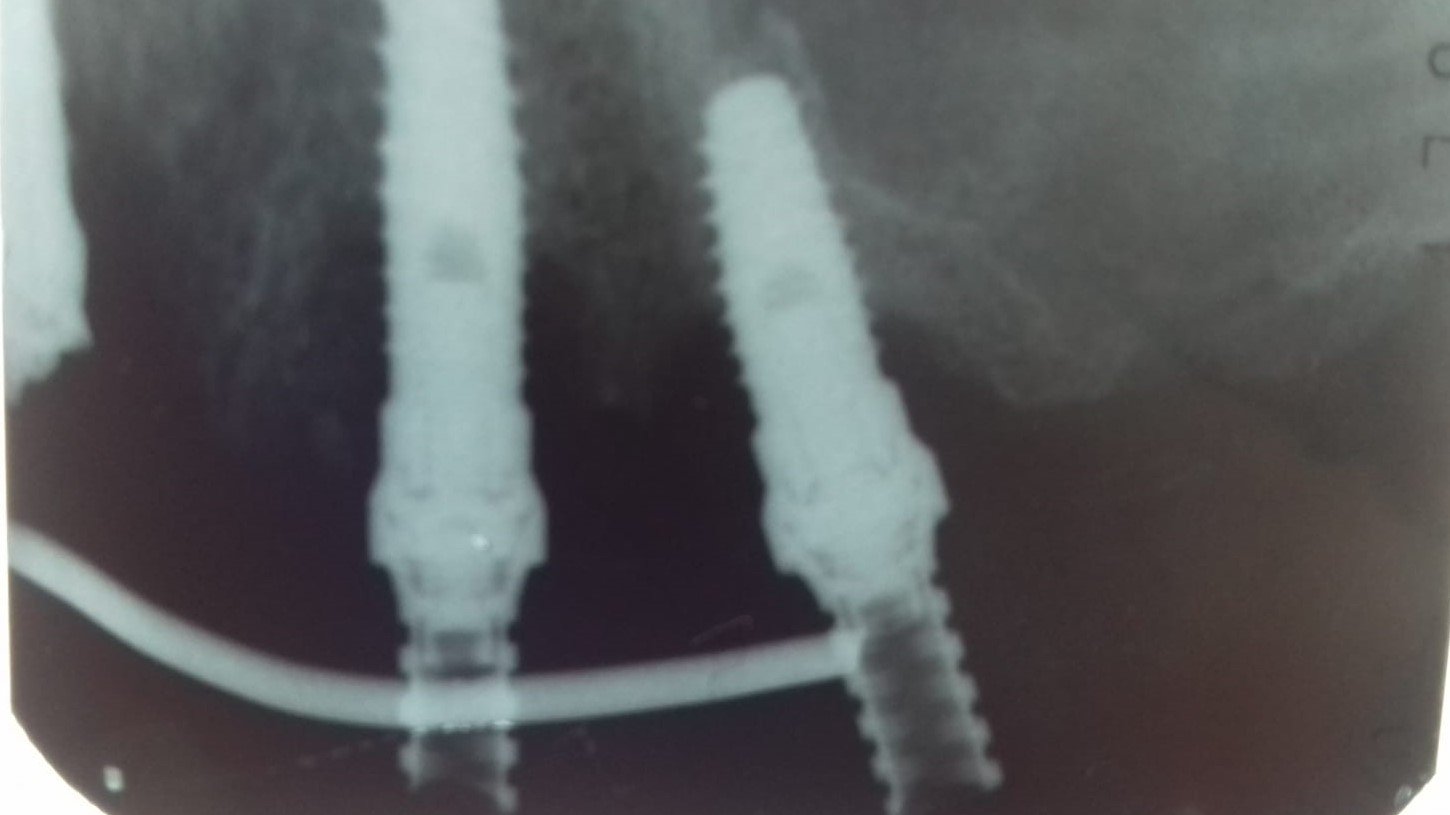

buenas,necesito vuestra ayuda,me manda la foto un clínico amigo para intentar averiguar que implante es,no tengo más datos

El paciente acude con una prótesis fija despegada de los pilares atornillados sobre esos implantes. Además, viene con el tornillo sobre el 23 roto y dentro del implante. Me gustaría [...]

Buenos días, colegas. Agradecería, por favor identificar este tipo de implantes, según el paciente llevan en boca unos 12 años. Cordiales saludos.

Al descubrir el acceso al tornillo es plano , no se que destornillador es.